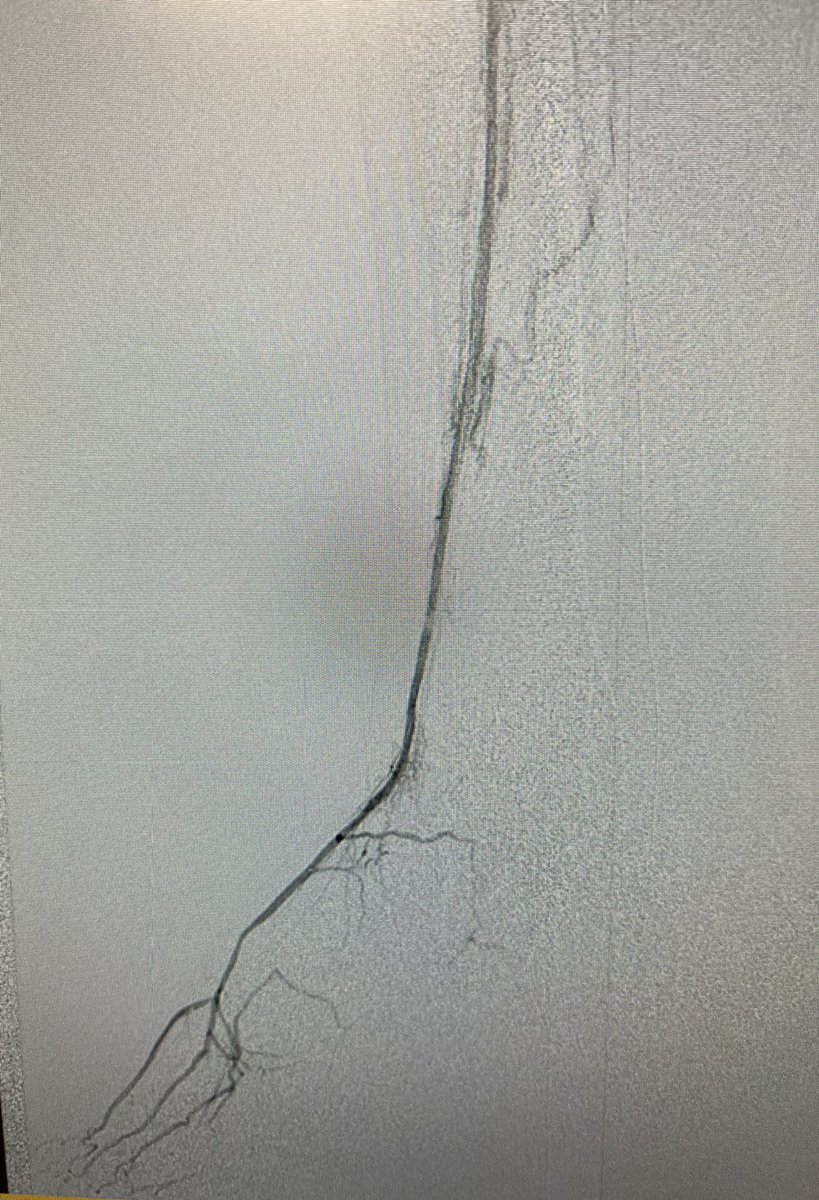

My best #DVA yet! Learning along. Venous pedal loop crossing crucial for success. Vein distention with contrast helps. Pull back injection helps with stent landing. Let the healing begin. Thx Fakhir Elmasri for assist! Society of Interventional Radiology SIR RFS #medtwitter PAIRS Society for Vascular Surgery

Staged Advanced Limb Salvage. Digital artery access to create outflow 1 vessel runoff from zero. Pt to come back for other tibial revasc. Society of Interventional Radiology American College of Cardiology Society for Vascular Surgery Anahita Dua MD MS MBA FACS Craig Walker, MD, FACC New Cardiovascular Horizons #Clifighters Eric Secemsky MD MSc CLI Global Society Seminars in Vascular Surgery

That feeling when your friendly podiatrist said he had 600 mL blood loss when working on your DVA patient 🩸 👍🏽 Society of Interventional Radiology SIR ECS CLIfighters